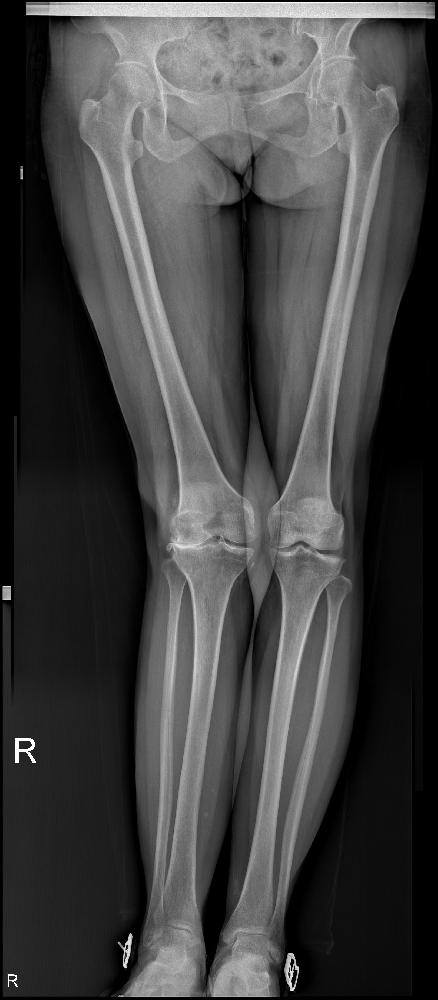

10年前,賈知梅的右膝關(guān)節(jié)開始疼痛,并伴隨著獨(dú)特的外翻畸形。這種痛苦持續(xù)了10年,時斷時續(xù),隨著勞累的增加而加劇。只有休息,她才能稍稍得到緩解;負(fù)重時,疼痛則變得更加明顯。為了緩解這種癥狀,賈知梅曾前往當(dāng)?shù)氐脑\所接受了針灸、按摩理療,效果也令她稍為舒服一些。

然而,一年前,賈知梅的右膝關(guān)節(jié)疼痛再度加重,甚至使她失去了行走的能力。在疼痛急劇惡化時,她只能依靠口服止痛藥稍稍緩解一些痛楚。面對這樣的困境,賈知梅選擇了市中區(qū)誠德骨科醫(yī)院入院,并接受了一項名為右膝外側(cè)固定平臺單髁置換術(shù)的手術(shù)。